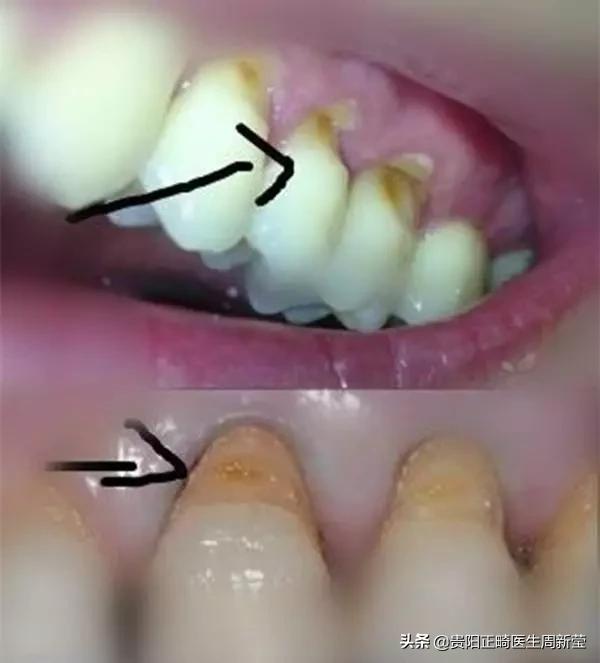

楔状缺损是指靠近脸颊和嘴唇一侧的牙颈部

因为缓慢而过量的磨耗而出现的楔形缺损

▲它长这样